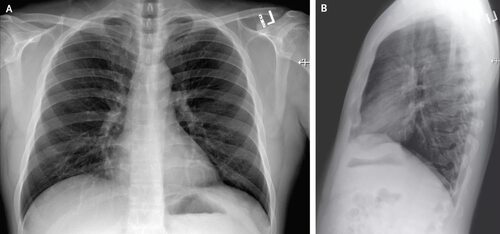

В этой статье мы собрали ряд рентген снимков легких, сделанных у пациентов, страдающих от коронавирусной инфекции. Фотографии помогут вам лучше понять проявления заболевания и его влияние на органы дыхания.

Ниже представлены несколько фотографий рентген снимков легких, сделанных при коронавирусной инфекции. Обратите внимание на характерные изменения, которые могут быть обнаружены на таких снимках:

- Различные степени поражения легких, включая пневмонию и другие воспалительные процессы.

- Появление темных пятен на снимках, указывающих на наличие инфекции и отека в легких.

- Сужение или расширение бронхов.

Обратите внимание, что рентген снимки легких являются одним из методов диагностики коронавируса, но не являются единственным. Для точного диагноза и назначения лечения требуется комплексное обследование и медицинская консультация.